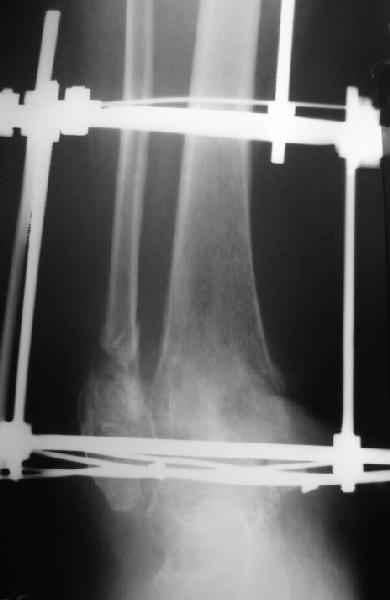

Пациентка 56лет поступила через 5,5 мес. после открытого 2-х лодыжечного перелома,

наружного вывиха правой стопы, осложнённого гнойным артритом.

через 3 недели после травмы в ОКБ выполнена артротомия, некрсеквестрэктомия б/берцовой

кости, ещё через неделю - аутодермопластика по Тиршу. К нам больная поступила через 5,5 мес.

Выполнен ЧКО, остеотомия м/берцовой кости, аппаратное вправление вывиха. Планируется

артродез голеностопного сустава. По медиальной поверхности голени на месте

аутодермопластики сформировался грубый рубец, спаянный с б/берцовой костью. Больная

ходит на костылях с частичной опорой на правую стопу. ВОПРОС: 1) возможно ли в данной ситуации

обойтись компрессионным артродезом в АВФ? 2) какой вид кожной пластики и в какие сроки

целесообразен?